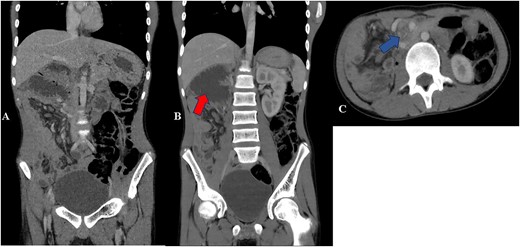

His laboratory results revealed a normal leucocyte count and hemoglobin of 12.2 g/dl. His serum sodium was 122.40 mmol/l and potassium was 2.57 mmol/l. Renal and liver function tests were within normal range as well as serum albumin and total protein. His abdominal ultrasound was normal. His esophageal-gastro-duodenoscopy showed normal mucosa with 2 l of bilious contents in the stomach; however, no obvious obstruction seen. His abdominal–pelvic computed tomography (CT) scan showed a severely dilated duodenum with a transition point at the superior mesenteric artery. Twisting of the mesentery seen around the superior mesenteric artery with ‘Whirlpool sign’ (Fig. 1). These features suggestive of midgut volvulus.

Contrast CT abdomen—coronal (A and B) and axial views (C) show small bowels on the right side of the abdomen and the large bowels on the left side of the abdomen. Image B shows distended duodenum (red arrow). Image C shows twisting of the mesentery and the superior mesenteric artery giving whirlpool sign appearance (blue arrow).

Midgut malrotation in adults may present as an acute abdomen that requires urgent intervention but may also present in non-acute setting with non-specific and chronic symptoms as our case, which include intermittent abdominal pain, bloating and food intolerance hence leads to increased morbidity and mortality [3]. This unspecific features cause delay in diagnosis similar to our case [3]. The acute features include midgut volvulus, small bowel obstruction and bowel ischemia [3]. Upper gastrointestinal series with oral contrast is the test of choice in the pediatric group along with Doppler ultrasound of the SMA; however, currently contrasted CT scan is the modality of choice showing ‘whirlpool’ sign as seen in Fig. 1 [4].